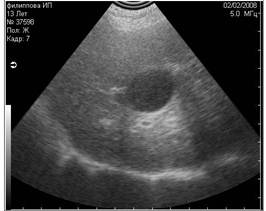

Рис3. Помехи, вызванные плохим выбриванием животного (продольные полосы слева). |

Рис 4. Недостаточное количество геля при проведении УЗИ (правая половина снимка). |